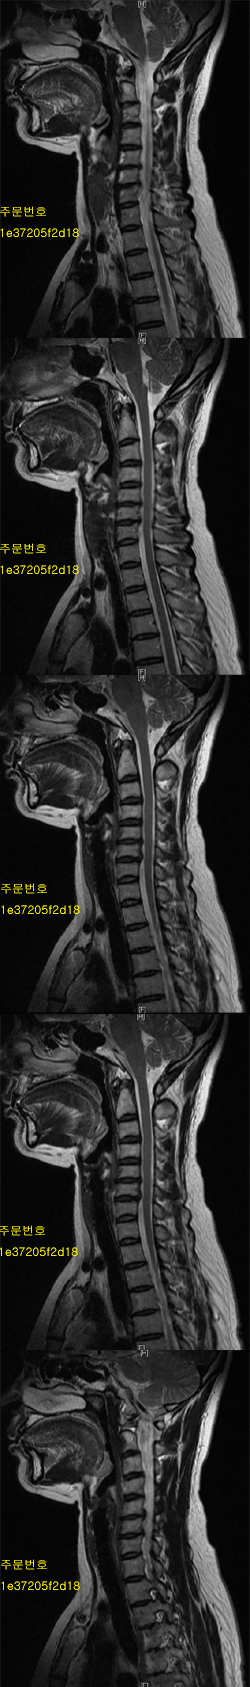

2007 7 Կ ̸ ´ ϰ Դϴ. --------------------------------------------------------------------- ȣϽų , ü Ư Ű 165 Cm ü 63 Kg 47 ȯ ǥغ ôĸε Ǵ ġȿ ū ϼŵ ϴ. ش Ͻø 㿡 ˴ϴ. ǥغ Ӹ ƴ϶ , , Ϗ ٸ Ͽ Ʒ شȯ ȣ˴ϴ. Ư ǥ ǥõ 10 ̳ ų ּȭ ˴ϴ. ǥ ǥõ ȯ̳ ð~ ̳ ȿ ֽϴ. ȯںе鲲 ϰ ü ǥغ ϸ鼭 ȯ ȣ ġ ִ Ȯϰ ֽϴ. ٸ ε ȯ ġϰų ġῡ Ǵ ôĻ· Ÿ μ Ÿ ִ Դϴ. ġᳪ ߹ Ͻô شǴ Ʒ ϼ. IJϰ üũϽø 㿡 ˴ϴ. 1C.ں, 1C.ټ Ǹ, 1C.ٱ (), 1C.߷ (), 2C., 2C.3C.̰( 2 ҿ) 3C.ڻ , 3C.ھ , 6C.ڸ , 6C. κ Ḳ , 6C.ھ Ḳ , 6C.ڻ , 6C.7C.ھ հ ̳ 7C.ڿʰ , 1T. κ , 1T.꿪 ĵ 1T.2T.3T.4T.6C.7C., , 2T. Ʒκ 5T.ȯ ҷ, 5T.ھ ȯ, 6T.ټ , 1L., 3L.ڽѻ Ǵ Ҽ, 3L.ڹ 3L. 4L Һ Һ, 4L.°Ű, 5L.ڴٸ Ʒκ̳ , 5L. ٸ, 5L. , õ().° ̳ , õ().ڱô (). ġ, ()κп ̻ ܵ. ()ũ( ߰Ż), ڸ(߹), ĿCڸ(ĸ), ߺο, ߺο, ũ(߰Ż)ġ, հ , ġ, , Ḳ ġ ʰ, װ Ǵ ġ ô Ʋ ¦ٸ(ٸ̰ ٸ) , 㸮 ̳ ġ ٸ ġ Ƹ ġ Ʈ 氨 ָ, ָ, ָ Ǵ ġ Ǵ ġ ƴ Ḳ ߰ Ḯ 3-4 ƽϴ. ܰ ġᵵ ް ѹ溴 ħ´µ غ غ ׳ ߵ Ҵµ ֱٿ ڱ(1-2) Ḳ հ ϴ. Ư ߶ ̻µ ڰ Ͼ Ѱ ӽϴ ۳ MRI() ܰ ׳ ġḸ ȴٰ ؼ Ҵµ ƹȿ ϴ. ֱ 6 䰡 ϰִµ ߴ ̾ X-ray µ ȸ ִٰؼ ġᵵ ƹȣ »· մϴ. ٸ 1997 ε °Ű̶ ߽ϴ װ͵ Ⱓ ٴϸ鼭 Ѿ ħ° ġް ߾ ״Դϴ. ȯ ȵǼ 10 Ҽ մϴ 1 6 Ҷְ 3-4 Ҷְ . ص 12ϰ ̳. 麸ñ ٰϴµ µ ʹ Դϴ. ̺Ժ ڸ鼭 ϴ 밡 Ůϴ. ------------------------------------------------------------------------------------------------ Ͻ 㳻 ù ߿ ȭ ٴ ¿ ȭ ǥظƮ ϼ̽ϴ. --------------------------------------------------------------- Ʈ 㳻 β ȭ · Ͽ ȣ 2~3 غ ٽ ܿ ص帮 ´ ü ŭ ɰ߾ 6~8 Ǿ · ȭ ҰԴϴ. |